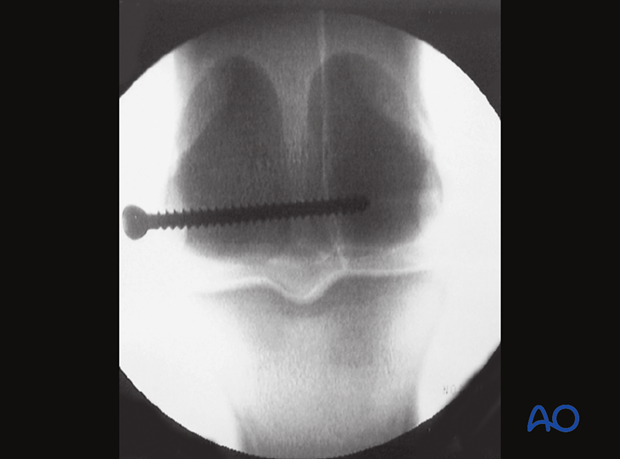

The screw is inserted but not fully tightened.

Ideally, a fluoroscopic view is taken to estimate if the screw length is correct. If correct, the screw is fully tightened. Some surgeons prefer to have the horse take weight off the limb while the final tightening is performed.